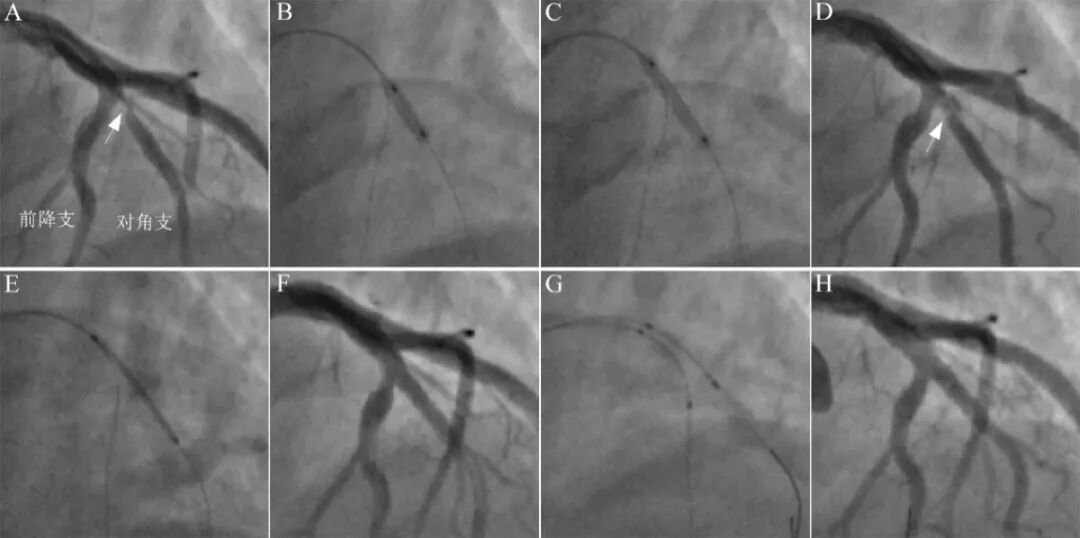

60岁女性,胸痛2个月。造影提示前降支近中段狭窄40-60%,粗大对角支开口狭窄95%(A)。首先尝试球囊处理,2.0mm半顺应性球囊和2.5mm切割球囊处理(B),对角支开口夹层形成,残余狭窄60%(C),决定直接采用双支架技术。鉴于对角支粗大,反观前降支略小+中段肌桥,决定采用反转Szabo双支架技术。主支远段(前降支中段)采用Szabo技术置入3.0×15mm药物洗脱支架(D-E),主支近段-对角支近段置入3.5×24mm药物洗脱支架(F),高压球囊对吻扩张(H),近端POT(I),最后结果良好(J)。